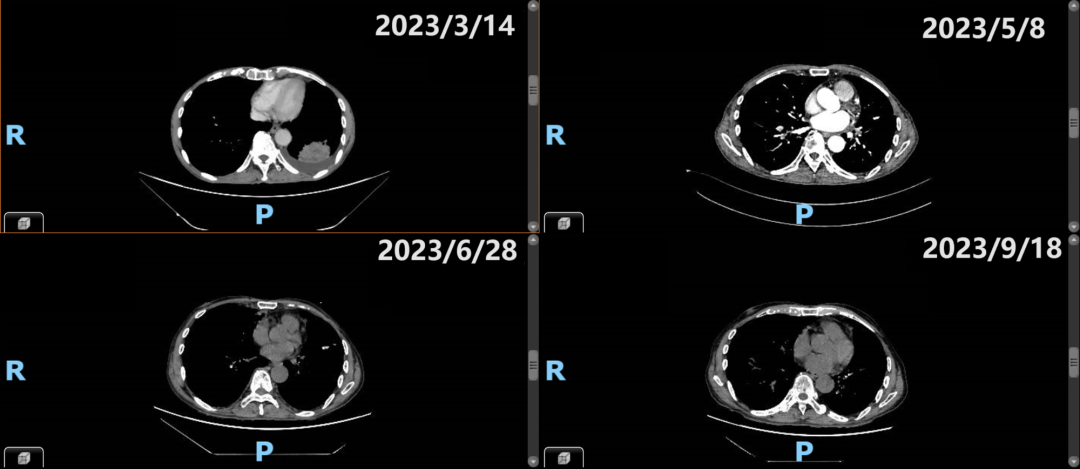

肺癌是全球发病率和死亡率最高的恶性肿瘤[1]。近年来,免疫联合化疗已成为晚期肺鳞癌患者的一线标准方案。斯鲁利单抗作为复宏汉霖自主研发的创新PD-1单抗,凭借ASTRUM-004研究出色的疗效数据于2022年10月获批晚期肺鳞癌一线治疗适应症。与此同时,世界肺癌联盟自2001年起将每年11月作为“全球肺癌关注月”,以提高人民防癌、抗癌意识,普及肺癌的规范化诊疗知识。值此之际,本报发起“晚期肺鳞癌一线免疫治疗病例征集”项目,希冀通过斯鲁利单抗肺鳞癌适应症获批上市一年来优秀病例的分享,为临床医生用药带来参考并提供交流的平台。 本期,我们分享一例一线使用斯鲁利单抗联合治疗使病情得到有效控制的高龄晚期肺鳞癌患者的病例,探讨真实临床实践中免疫治疗在肺鳞癌患者中的用药模式及价值。 钟敏 博士 南昌大学第一附属医院呼吸与危重症医学科 主治医师 2022届优秀博士毕业生 江西省整合医学学会肿瘤分会委员 江西省整合医学学会肿瘤免疫治疗分会委员 研究方向:呼吸系统肿瘤综合治疗 主持国家自然科学基金1项,参与国家自然科学基金多项 主持江西省自然科学基金、卫健委、教育厅等省厅课题4项 以第一作者发表SCI论文6篇,其中影响因子>5分4篇 一般情况:男性,86岁 主诉:反复咳嗽咳痰4月余。 首诊日期:2023-03-14 现病史:患者4月余前无明显诱因下出现咳嗽咳痰,伴间断发热,体温最高38.1℃,无咳血,无胸闷、胸痛、呼吸困难等症状。症状反复发作,呈进行性加重。2022年11月至当地医院完善胸部CT考虑肺部肿瘤可能,予以抗感染、对症支持治疗无明显好转。2023年2月17日复查胸部CT示两肺多发结节肿块,对比当地2022年11月CT较前明显进展,由于患者老龄,心肺功能差,建议保守治疗。患者为行进一步治疗来我院就诊,门诊拟“肺占位性病变”收治入院。患者自发病来,精神、饮食、睡眠稍差,大小便正常,体重下降5 kg。 既往史:平素健康状况一般。有糖尿病史,患病10余年,服药情况瑞格列奈三餐前1片,胰岛素早上15单位,有结核病史,患病2月,未服药;否认高血压病史,否认肝炎病史,否认输血史,否认药物过敏史,否认其他药源性疾病,否认食物过敏史,否认食物中毒史,否认外伤史。有手术史,2018年行胃动脉破裂修补术,10余年前行疝气手术。否认其他重大疾病史。预防接种史不详。 个人史、婚育史、家族史无特殊。 辅助检查 2023-03-14 实验室检查:肿瘤标志物水平升高,鳞状细胞癌相关抗原 21.30ng/mL、细胞角蛋白19片段 26.70ng/mL,神经特异性烯醇化酶(NSE) 20.20ng/mL。 2023-03-14 胸部增强CT:1.双肺慢支肺气肿,两肺散在感染性病变,部分偏慢性感染,建议治疗后短期复查。2.左上肺异常肿块伴阻塞性改变,考虑左上肺癌并左上肺不张,请结合临床及纤支镜检查;左下肺肿块,考虑恶性、转移可能;两肺多发结节,需考虑肺内转移可能性大;纵隔淋巴结转移可能。3.左侧胸腔少量积液。 2023-03-14 心电图、心肺功能:未见特殊异常。 2023-03-15 肺穿刺病理:(左肺穿刺组织)活检组织,中分化鳞状细胞癌。免疫组化示:CK5/6(3+);P63(+);P40(+);CK7(-);TTF-1(-);NapsinA(-);Ki-67(40%+);NUT(-);CD117(-);C-erbB-2(0);CEA(-)。特殊染色示:PAS(-)。肿瘤细胞PD-L1表达水平:TPS评分50%。 病理组织形态学及免疫组化结果 诊断 肺鳞癌(T4N2M1)(PD-L1高表达) 纵隔淋巴结继发恶性肿瘤 肺继发恶性肿瘤 糖尿病 胸腔积液 治疗经过 一线治疗: 治疗方案为PD-1单抗(斯鲁利单抗300mg)联合重组人血管内皮抑制素治疗。 一线治疗疗效评估: 影像学检查: 2023-05-08胸部CT(治疗2周期后):左上肺近肺门少许软组织影,较前明显缩小,左肺上叶较前复张;左下肺肿块,较前缩小,两肺多发结节,右下肺部分结节较前缩小。 用药2周期后疗效评价为PR。 2023-06-28胸部CT(治疗4周期后):左上肺近肺门软组织影,较前缩小;左下肺肿块,较前缩小;两肺多发结节,右下肺部分结节较前缩小,需考虑转移,余结节变化不大,左侧胸腔少量积液,较前有所吸收。 用药4周期时疗效评价为PR。 主病灶影像学变化 转移灶影像学变化 实验室检查: 鳞状细胞癌相关抗原、细胞角蛋白19片段、NSE水平明显下降。 肿瘤标志物水平变化趋势 甲状腺功能未见明显异常。血常规、肝肾功能、心肌酶、电解质未见明显异常。 总体疗效评估:PR 不良反应: 一线治疗用药安全性良好,未发生皮肤及皮下组织、内分泌系统、肝功能、肺部疾病、血液系统等用药相关不良反应。 该患者为一位86岁老年男性,因“反复咳嗽咳痰4月余”入院。患者4月余前无明显诱因出现咳嗽咳痰,伴间断发热。症状反复发作,呈进行性加重。2022年11月曾于外院予以抗感染、对症支持治疗,无明显好转。2023年2月外院检查考虑肺部肿瘤,但鉴于患者老龄,心肺功能差,建议保守治疗。患者来我院就诊后,完善相关实验室及影像学检查,确诊患者为肺鳞癌(分期:T4N2M1,PD-L1 TPS为50%),伴肺部多发转移、纵隔淋巴结转移。同时患者合并有糖尿病和胸腔积液。 根据2023年中国临床肿瘤学会(CSCO)非小细胞肺癌(NSCLC)指南推荐,对于该类Ⅳ期无驱动基因、一般状况较差的肺鳞癌患者,可给予化疗联合方案、免疫单药方案或免疫联合化疗方案[2]。ASTRUM-004研究作为斯鲁利单抗探索NSCLC免疫治疗的里程碑研究[3],展现了斯鲁利单抗优越的疗效和良好的安全性,2023 CSCO指南由此将斯鲁利单抗联合方案纳入I级推荐。本例真实世界中的患者86岁高龄,且具有合并症,因此采用斯鲁利单抗联合非化疗方案治疗,2周期后即评价为PR,并在4周期时维持PR,且安全性良好,病情得到持久缓解。 周菁 教授 南昌大学第一附属医院 呼吸与危重症医学科 副主任医师 副教授 医学博士 硕士研究生导师 美国圣路易斯华盛顿大学医学院 访问学者 中国医师协会变态反应医师分会委员 江西省医师协会呼吸医师分会常委 江西省整合医学会肺癌分会常委 江西省保健学会呼吸病学分会常委 江西省呼吸专科医联体常务理事 江西省抗癌协会呼吸介入专业委员会委员 华东地区介入呼吸病协作组青年委员会委员 中国医药教育协会介入微创呼吸分会委员 与肺腺癌相比,肺鳞癌患者的吸烟患者比例更高,且驱动基因突变率更低,5年总生存期(OS)也明显更低[4]。由于已知基因突变较少,肺鳞癌靶向治疗存在较大局限性。在这种情况下,既往肺鳞癌主要以传统化疗为主,但多项证据提示,一线化疗带给患者的生存获益十分有限,OS难以超过1年[5]。 近年来随着免疫治疗在肿瘤领域的探索和应用,肺癌患者迎来更多更好的治疗选择。随着KEYNOTE-407、CheckMate-227、IMpower131等多项研究的开展,人们发现,免疫治疗联合治疗用于晚期肺鳞癌患者的一线治疗,表现出显著优于传统化疗的长生存获益。一线免疫联合化疗方案能为晚期肺鳞癌患者带来超过20个月的OS获益,PFS也提升至8个月及以上。 斯鲁利单抗在ES-SCLC一线治疗领域取得突破性成果,刷新ES-SCLC免疫治疗生存纪录,引起临床医生广泛关注。同时,斯鲁利单抗在肺鳞癌领域同样表现不俗。ASTRUM-004研究作为一项全球多中心、随机、双盲对照Ⅲ期研究[3],近期由周彩存教授在世界肺癌大会(WCLC)上进行口头报告。研究纳入组织学或细胞学确诊的不能手术或放疗的ⅢB/ⅢC或Ⅳ期鳞状NSCLC患者共537例,其中359例受试者来自中国。在研究主要终点方面,斯鲁利单抗联合化疗组的全人群中位PFS为8.3个月,降低疾病进展或死亡风险达45%,且亚裔人群获益更为突出,PFS达9.9个月,创同类产品Ⅲ期研究的最长纪录。关键次要终点方面,全人群组的中位OS达22.7个月(对照组为18.2个月,HR=0.73,95%CI 0.58~0.93;P=0.010,达到显著性阈值0.046),校正交叉影响后,OS较对照组延长达11.2个月[6]。目前亚裔人群组的最终OS结果已投稿国际学术大会,数据值得期待。 本例患者高龄,同时有糖尿病史和胸腔积液,肿瘤标志物升高,一般状况较差。2016年的一项研究[7]曾提示,大于80岁的EGFR非突变型NSCLC患者PFS仅1.9个月,OS仅4.9个月。因此这类患者对于治疗药物的疗效和安全性均有较高的要求。从该患者较高的年龄和较差的一般情况分析,无法耐受标准的双药化疗方案。而生物学特征上TPS评分50%,属于KEYNOTE-024研究中显示的PD-1单抗治疗获益人群,有获得长期缓解的机会。综合考虑ASTRUM-004研究中斯鲁利单抗的优秀疗效和可控的安全性,因此制定了斯鲁利单抗联合治疗方案。在实践中观察到产品的疗效和安全性良好,验证了临床实践表现与ASTRUM-004研究一致。 参考文献 1. Alesha A Thai, et al. Lancet . 2021 Aug 7;398(10299):535-554. 2. 2023 CSCO非小细胞肺癌诊疗指南. 3. 斯鲁利单抗说明书. 4. Bing-Yen Wang, et al. J Cancer Res Clin Oncol . 2020 Jan;146(1):43-52 5. Thatcher N, et al. Lancet Oncol 2015;16:763-774. 6. WCLC 2023 - OA09晚期NSCLC的免疫治疗 (abstractsonline.com) 7. Chen Yu-Mu, et al. Lung Cancer, 2016, 98: 99-105.